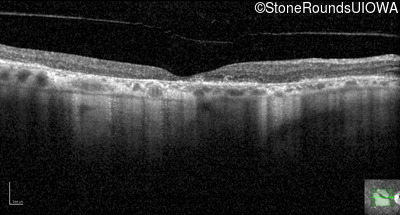

Optical Coherence Tomography - Left - 20/40 +2

Exemplar / OCT Stack